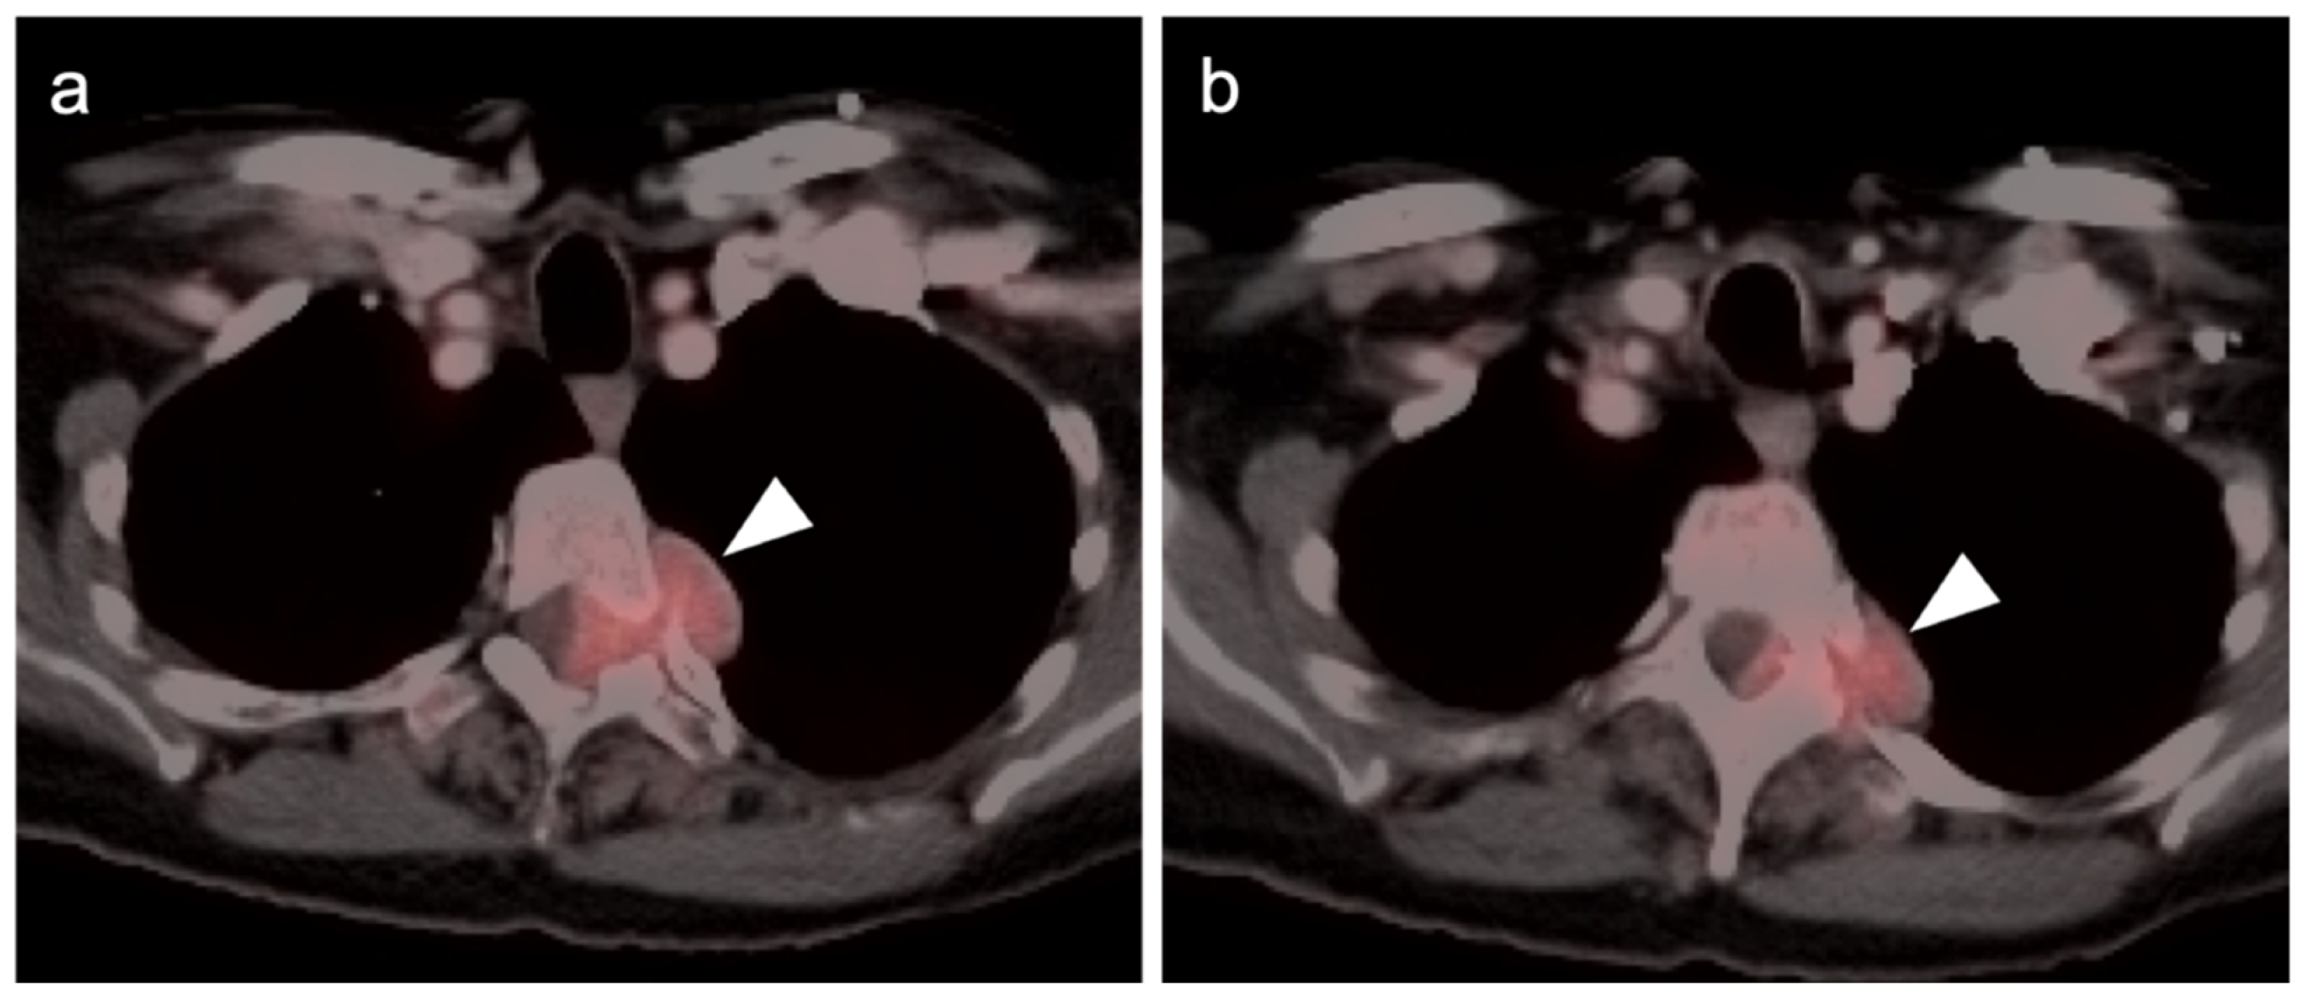

2.3.2. Ocular Melanoma

2.3.3. Mucosal Melanoma